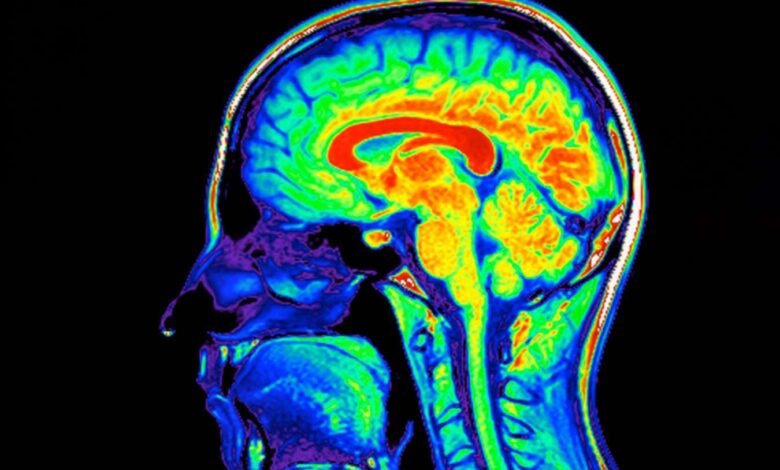

Magnetic resonance imaging scan of a human brain

Phanie/Sipa Press/Alamy

A device that massages the face and neck boosts the brain’s waste disposal system, suggesting it could reduce the severity of conditions like Alzheimer’s disease.